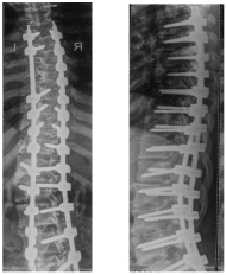

Ретроспективный анализ показал, что наибольшая величина коррекции наблюдалась у пациентов, которым применяли I вариант оперативного лечения. После хирургического вмешательства остаточная деформация сколиотической дуги деформации составила от 0 ° до 17 ° (средняя величина остаточной деформации - 7 °), процент коррекции колебался от 74 % до 100 % (средний процент коррекции - 86,6 %). Остаточный угол ротации апикального позвонка составил от 10 ° до 27 ° (средний остаточный угол ротации 18,5 °). Средний процент деротации апикального позвонка составил 24,4 % (рис. 2 А, Б). Такие результаты лечения объясняются наличием сколиотической деформации, не превышающей 85 °, мобильной сколиотической дугой искривления и применением в качестве опорных элементов спинальной системы с транспедикулярными опорными элементами. Тотальная транспедикулярная фиксация, используемая при коррекции сколиотической деформации, позволила осуществить равномерное распределение нагрузки вдоль опорных элементов металлоконструкции и предотвратить в дальнейшем потерю коррекции достигнутого результата в послеоперационном периоде наблюдения.

А

Б

Рис. 2. Рентгенограммы позвоночника пациентки К., 16 лет. Идиопатический левосторонний грудопоясничный сколиоз IV степени: А - до операции, угол деформации 70 ° по Cobb; Б - после операции, угол деформации 17 ° по Cobb